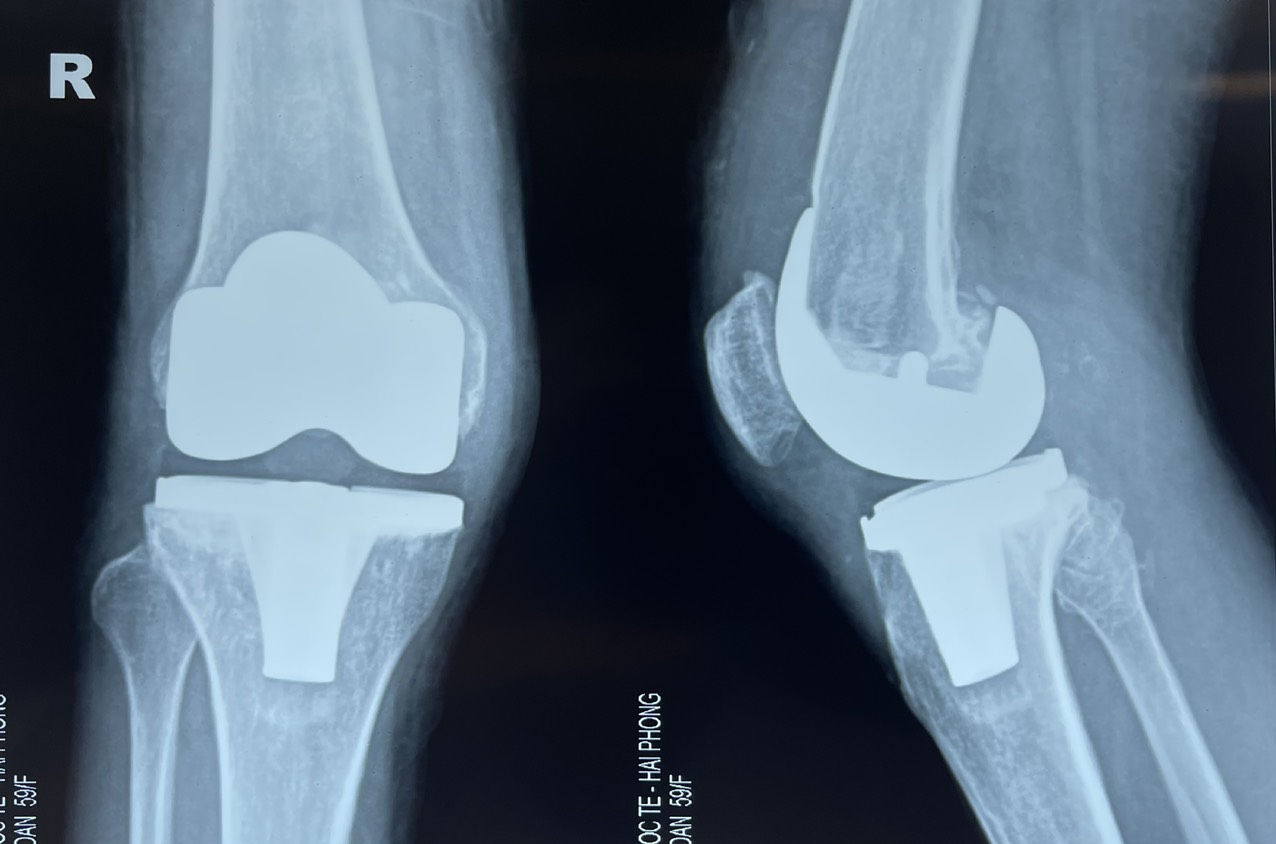

Hình ảnh Xquang gối phải bị thoái hóa nặng của bệnh nhân

Theo BSCKI. Nguyễn Đức Hòa – Khoa Ngoại Chấn Thương Chỉnh Hình, Bệnh viện đa khoa Quốc tế Hải Phòng: Đây là một trường hợp phẫu thuật khó vì bệnh nhân đã bị đau và biến dạng gối phải nhiều năm, toàn bộ bề mặt khớp gối phải đã bị hư hỏng nặng, xương mặt khớp mâm chày bị sập làm lệch trục chi chân phải. Để giải quyết ca bệnh cần chú ý hai vấn đề chính đó là: chỉnh trục chi chân phải và cân bằng phần mềm. Vì vậy trước mổ phẫu thuật viên cần tính toán thật chi tiết và chuẩn bị đầy đủ các phương án xử lý trong mổ phù hợp.